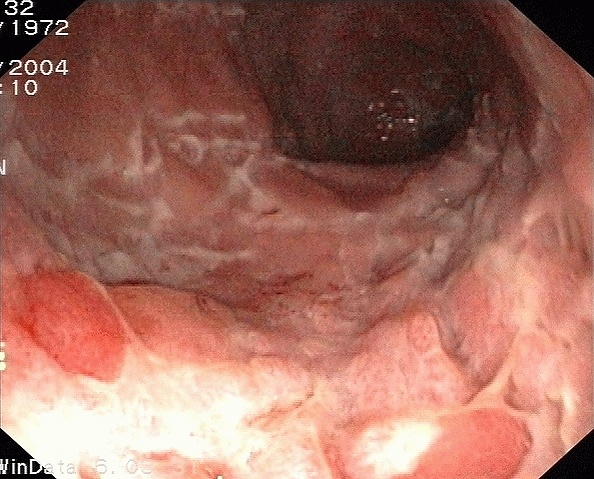

Болезнь Крона может поражать любой отдел пищеварительного тракта, но всё же в 2/3 случаев процесс локализуется в терминальном отделе подвздошной кишки и начальном отделе толстого кишечника. Характерно сегментарное поражение кишечника, имеющее чёткую границу с соседними здоровыми отрезками. Стенка утолщена, просвет сужен, кишка расширена перед поражённым участком. Слизистая оболочка с многочисленными продольными, щелевидными язвами и поперечными трещинами, бугристая, имеет вид «булыжной мостовой». В некоторых случаях происходит перфорация язв с образованием внутрибрюшинных абсцессов и свищей. Свищи могут сообщаться с петлями кишечника и окружающими органами (мочевой пузырь, матка и влагалище у женщин, кожа).

- Колоноскопия и эндоскопия c биопсией подтверждают диагноз гистологически. В настоящее время «золотым стандартом» диагностики болезни Крона является проведение илеоколоноскопии (то есть осмотра всей толстой кишки и терминального, конечного, отдела подвздошной кишки), поскольку это заболевание поражает не только толстую кишку, но и вышележащие отделы. Обязательным условием является забор множественных биоптатов из всех отделов толстой кишки (не менее 2-х) и подвздошной кишки (как поражённых, так и интактных) с последующим гистологическим исследованием биоптатов. Важным является запись исследования на дисковый носитель, что в дальнейшем является своеобразным «вещественным доказательством» при наличии спорного диагноза. Наличие видеозаписи позволяет не проводить повторное исследование пациенту без необходимости. Особо следует отметить необходимость проведения илеоколоноскопии с гистологическим исследованием биоптатов до начала лечения (если это позволяет состояние пациента), чтобы не «смазать» эндоскопическую и морфологическую картину. Значимым прогрессом в диагностике болезни Крона тонкой кишки является использование эндокапсулы, что позволяет осмотреть тонкую кишку, однако при этом отсутствует возможность забора биоптата.